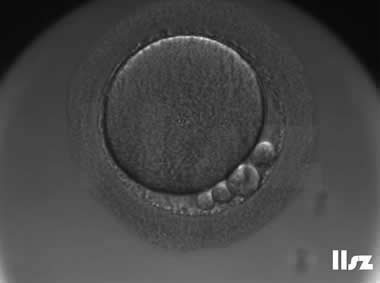

3. 成熟卵母细胞(MII)及其COCs(正常COCs)

卵细胞呈现规则的圆形且颜色较浅,放射冠完全分散,颗粒细胞团较大,排列稀疏。成熟卵母细胞一般在取卵后体外培养2-6小时再行授精。

|  |

| 0小时COCs的MII卵(4x) | 0小时COCs的MII卵(10x) |

|  |

| 2小时COCs的MII卵(10x) | 4小时去颗粒细胞后的MII卵(10x) |